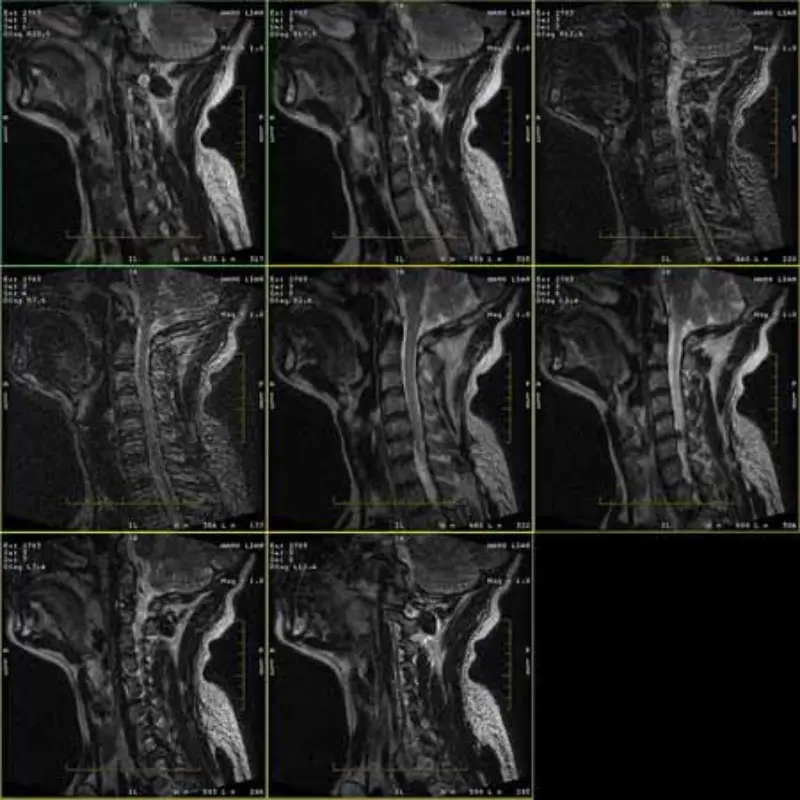

FRFSE və GRE protokollarının təsvirləri xəyala malikdir və bəzən aşağı SNR şəkilləri bir seriyada görünür. Lakin SE protokol şəkilləri normaldır.

Zəhmət olmasa şəkillərə baxın.